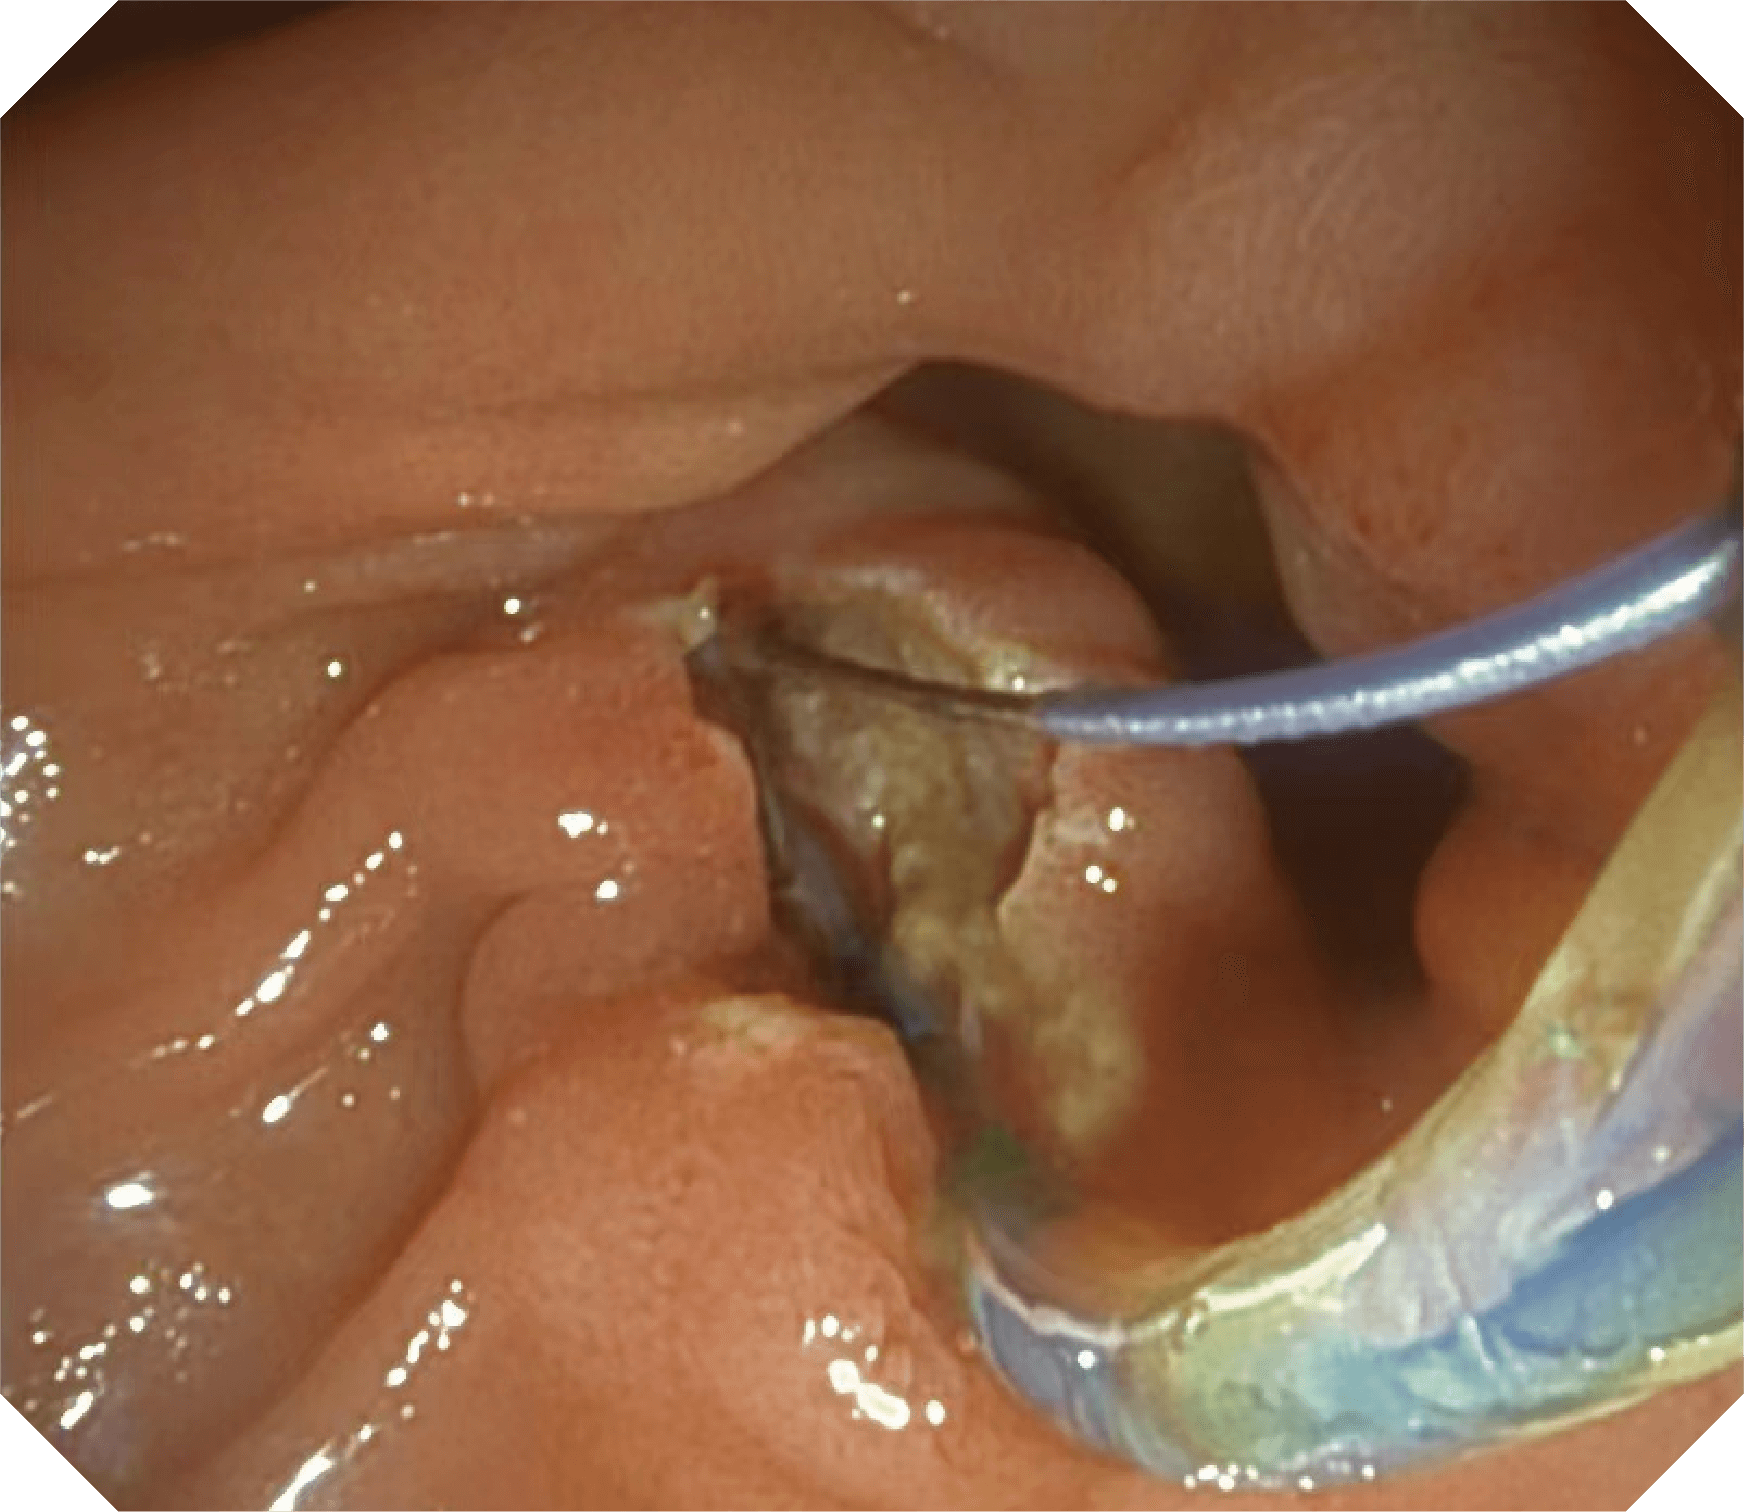

4.2mm大钳道,器械交换更顺畅

卓越的抬钳器控制

导丝机械锁紧功能

V槽设计提升导丝控制

优异的手术器械抬举性